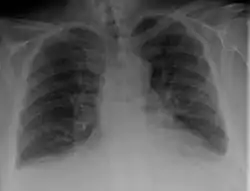

Chest X-ray

Chest X-rays are frequently used to aid in the diagnosis of CHF. In a person who is compensated, this may show cardiomegaly (visible enlargement of the heart), quantified as the cardiothoracic ratio (proportion of the heart size to the chest). In left ventricular failure, there may be evidence of vascular redistribution ("upper lobe blood diversion" or "cephalization"), Kerley lines, cuffing of the areas around the bronchi, and interstitial edema. Ultrasound of the lung may also be able to detect Kerley lines.[39]

-

Congestive heart failure with small bilateral effusions. -

Kerley b lines.